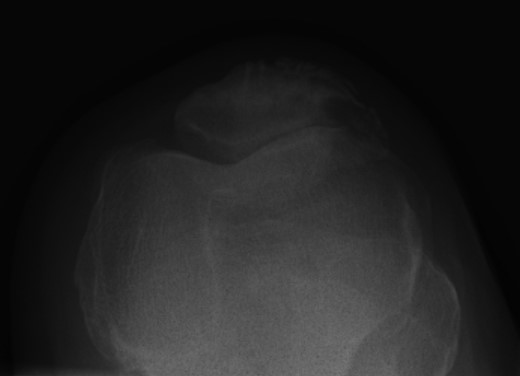

Nineteen months earlier the patient had consulted his general practitioner complaining of left knee pain. Radiographs performed at that time were reported to show joint space narrowing within the patello-femoral compartment as well as early joint space narrowing within the medial compartment. A subchondral lucency was also noted within the patella which was described as a subarticular cyst secondary to the previously mentioned patello-femoral degeneration (Figs 1–3).